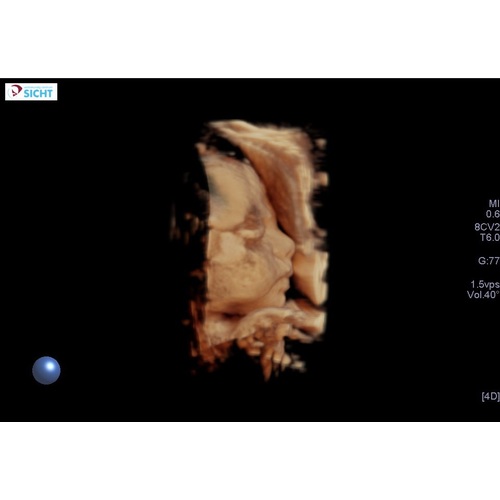

Staan ze er vanavond ook ? En wat kost het als ik vragen mag ? Wij hebben deze met 28 weken een 3D echo laten maken..zoooo speciaal. Bijna verslavend, dus zou het zo weer willen doen. Al denk ik dat het voor mij te laat is. 33weken, zal lastig worden om haar goed in beeld te krijge

Ze staan er volgens mij elke dag! Kost 50 euro krijg je twee foto's geprint en een USB stick met alle foto's. ( Het is trouwens ook allemaal voor je goede doel ) Ik vond het echt leuk en de moeite waard ook al zie je nog niet hoe de baby er verder precies uitziet. Juist een toffe ervaring en doe het met 28 weken gewoon weer